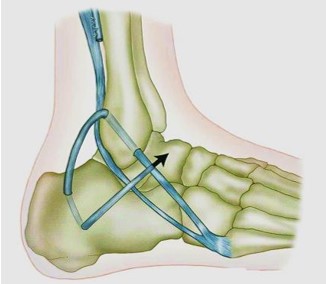

Тенодез Крисмана-Снука заключается в восстановлении передней таранно-малоберцовой и пяточно-малоберцовой связок и на сегодняшний день является, наверное, наиболее популярным методом неанатомической реконструкции связок голеностопного сустава (рис. 7.5). При этой операции выделяется и разделяется продольно сухожилие короткой малоберцовой мышцы, после чего половина сухожилия применяется для реконструкции обеих связок. В одном из исследований показано, что удовлетворительные результаты после такого типа вмешательства наблюдаются у 94% пациентов (Snook et al. 1985). При стресс-тестах остаточная нестабильность голеностопного сустава после операции Крисмана-Снука также выражена в меньшей степени, чем после операции Эванса. Операция в техническом отношении более требовательна по сравнению с другими тенодезами.

Рис. 7.5 Тенодез Крисмана-Снука